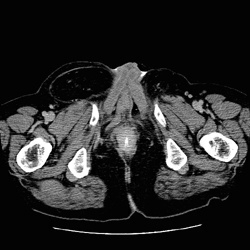

RADIOLOGY: GENITOURINARY: GU: Case# 33088: BLADDER EXTROPHY